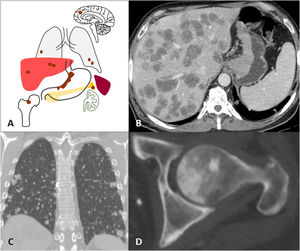

Since the stomach drains through the portal venous system, haematogenous metastases most commonly occur in the liver. Clinical guidelines recommend CT and sometimes PET-CT as the imaging tests of choice for the detection of metastases3,48. However, the detection of liver metastases by MRI has increased in recent years. A recent review and meta-analysis demonstrated that the sensitivity of contrast-enhanced MRI with liver-specific agents was higher than that of intravenous contrast-enhanced CT for the detection of liver metastases in primary gastrointestinal and colorectal neoplasms, especially in lesions smaller than 10mm21. Liver metastases of GAs are usually hypovascular and present as nodular hypodense lesions on CT. On MRI, restricted diffusion in Diffusion-Weighted Imaging and low signal in the hepatobiliary phase following the administration of a liver-specific contrast agent are the main diagnostic features for the detection of liver metastases18,21,49. Other possible sites of GA metastasis are the lungs, bone, the adrenal glands or CNS (Fig. 8)1.